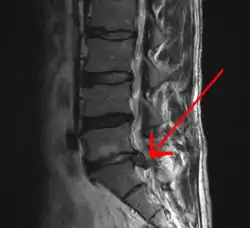

An intervertebral disc has a gelatinous core surrounded by a fibrous ring.[37] When in its normal, uninjured state, most of the disc is not served by either the circulatory or nervous systems – blood and nerves only run to the outside of the disc.[37] Specialized cells that can survive without direct blood supply are in the inside of the disc.[37] Over time, the discs lose flexibility and the ability to absorb physical forces.[28] This decreased ability to handle physical forces increases stresses on other parts of the spine, causing the ligaments of the spine to thicken and bony growths to develop on the vertebrae.[28] As a result, there is less space through which the spinal cord and nerve roots may pass.[28] When a disc degenerates as a result of injury or disease, the makeup of a disc changes: blood vessels and nerves may grow into its interior and/or herniated disc material can push directly on a nerve root.[37] Any of these changes may result in back pain.[37]

Imaging is indicated when there are red flags, ongoing neurological symptoms that do not resolve, or ongoing or worsening pain.[5] In particular, early use of imaging (either MRI or CT) is recommended for suspected cancer, infection, or cauda equina syndrome.[5] MRI is slightly better than CT for identifying disc disease; the two technologies are equally useful for diagnosing spinal stenosis.[5] Only a few physical diagnostic tests are helpful.[5] The straight leg raise test is almost always positive in those with disc herniation,[5] and lumbar provocative discography may be useful to identify a specific disc causing pain in those with chronic high levels of low back pain.[46] Therapeutic procedures such as nerve blocks can also be used to determine a specific source of pain.[5] Some evidence supports the use of facet joint injections, transforminal epidural injections and sacroiliac injections as diagnostic tests.[5] Most other physical tests, such as evaluating for scoliosis, muscle weakness or wasting, and impaired reflexes, are of little use.[5]